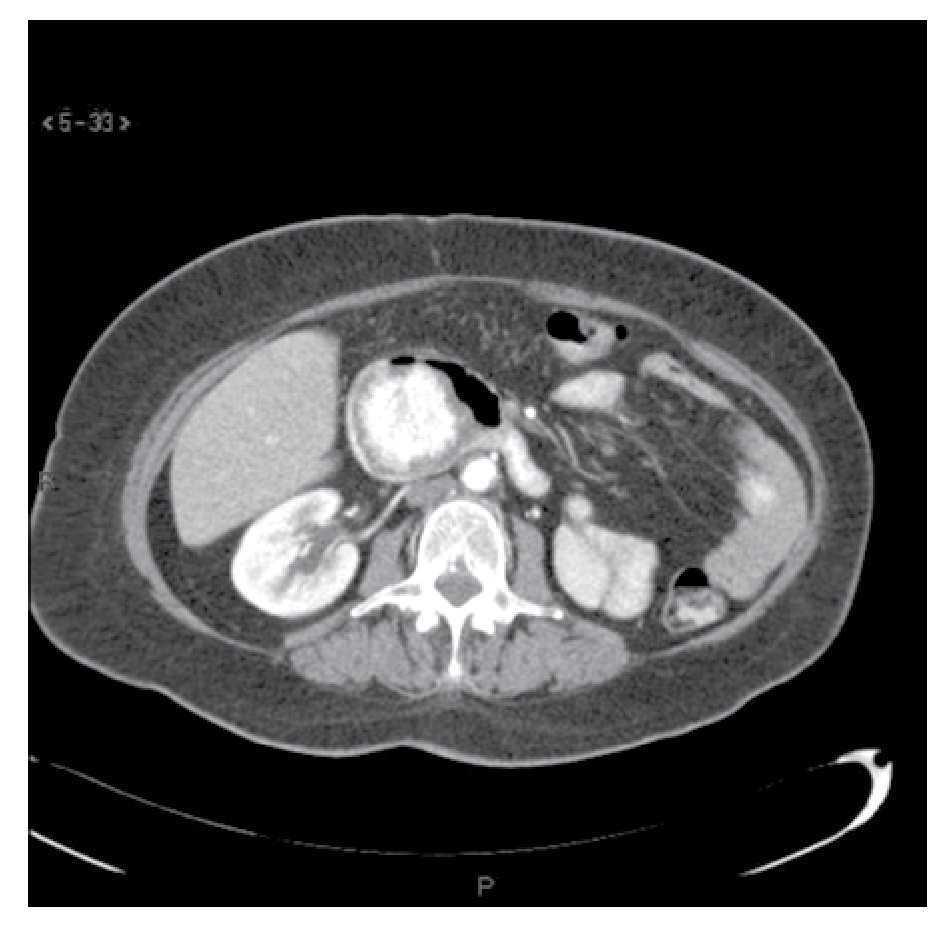

Caso 2. Una mujer de 68 años de edad con historia de nefrectomía izquierda por CaRCC seis años y medio antes del inicio de su padecimiento actual. Fue referida a nuestro Instituto por presentar STDA y dolor epigástrico. La paciente traía consigo un estudio endoscópico que revelaba una neoplasia en la segunda porción del duodeno, del cual no se obtuvieron biopsias. A su llegada se le realizó una tomografía helicoidal (Figura 2) que mostró una masa intraluminal hipervascular en la segunda porción del duodeno. Por este motivo se decidió realizar una PD clásica. La paciente egresó luego de 10 días de estancia intrahospitalaria sin presentar complicaciones. Ha permanecido asintomática y sin evidencia de enfermedad tras 34 meses seguimiento posoperatorio.

¿ Figura 2. Tomografía abdominal con contraste intravenoso en fase arterial, demostrando una masa intraluminal hipervascular en la segunda porción del duodeno. También se observa ausencia del riñón izquierdo.